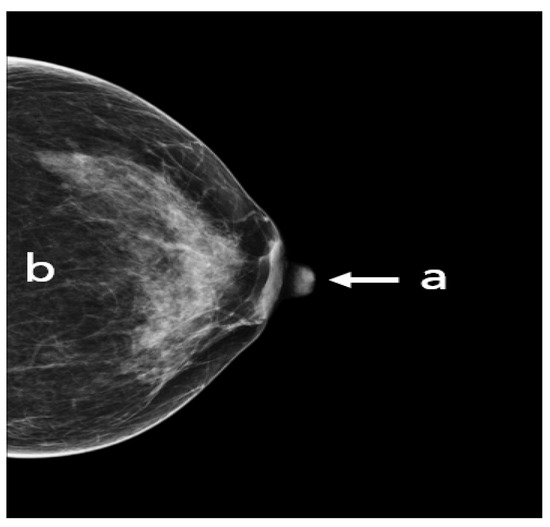

A standard view taken from the medial upper end to the lateral lower end at an angle of approximately 45° (Figure 4). It represents the most important projection as it allows visualization of the upper outer quadrant with the greatest amount of breast tissue. In an adequate MLO view, as shown in Figure 5, the pectoralis muscle should be relaxed, imaged to the nipple level (a) and convex or straight, with an angle of a least 10° (b), the nipple must be in profile (c), and all the breast tissue and the retroglandular fat should be clearly shown (d), with no skin folds present.

Figure 5. An adequate MLO view with (a) pectoralis to nipple level, (b) relaxed with an angle > 10°, (c) nipple in profile, and (d) visualized retroglandular fat.